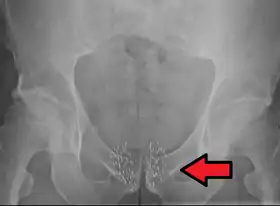

Arrow points to brachytherapy beads used to treat prostate cancer.